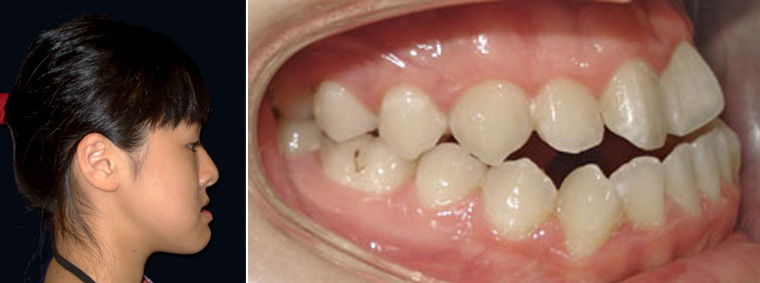

在台灣有許多幼童在青春期前期,即呈現了「亞當氏症候群」的病症。「亞當氏症候群」出現明顯的「鼻腔過敏」、「鼻塞」、「口呼吸」、「下顎骨生長不全」、「上唇與上面的牙齒外暴」與「嘴唇水腫」,這類臉型的異常在外觀上呈現不協調平衡的狀態(圖15)。

(圖15)在台灣有許多幼童在青春期前期,即呈現了「亞當氏症候群」的病症。「亞當氏症候群」出現明顯的「鼻腔過敏」、「鼻塞」、「口呼吸」、「下顎骨生長不全」、「上唇與上面的牙齒外暴」與「嘴唇水腫」,這類臉型的異常在外觀上呈現不協調平衡的狀態。

如果「亞當氏症候群」可在青春前期及早被發現治療 ,可藉由治療刺激與增加下顎骨的前向生長(圖16)。

(圖16)如果「亞當氏症候群」可在青春前期及早被發現治療 ,可藉由治療刺激與增加下顎骨的前向生長。